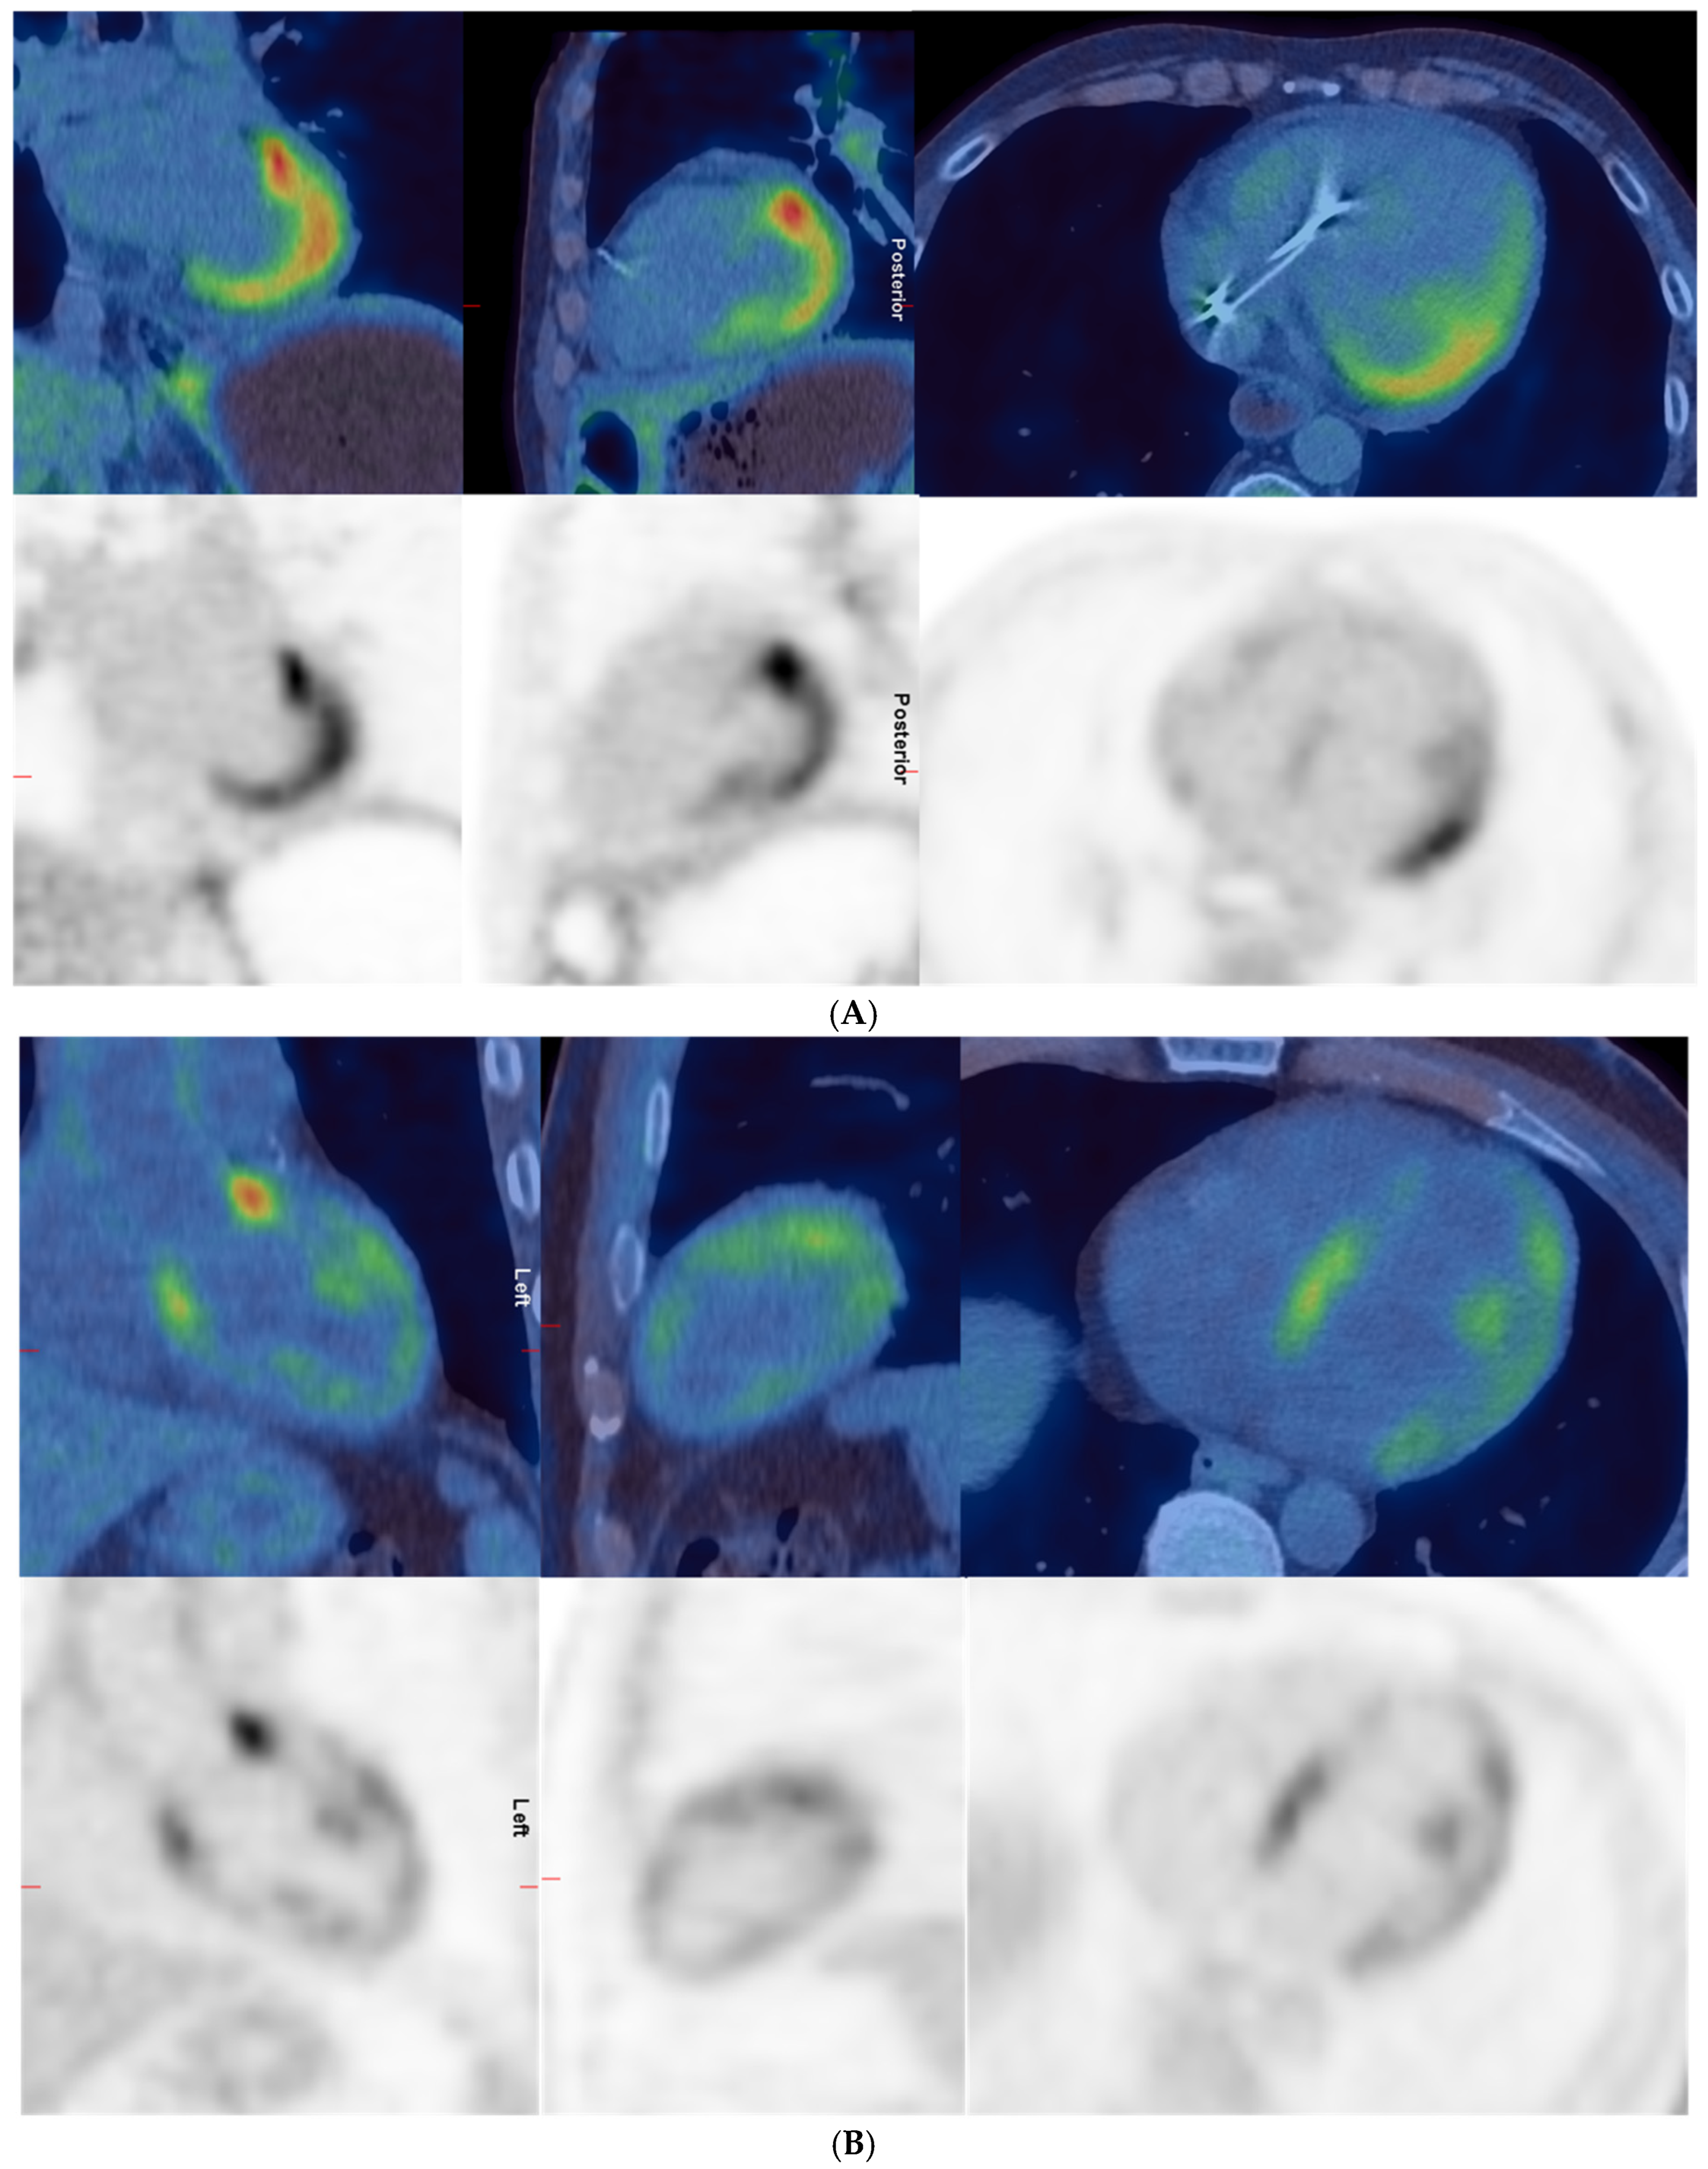

| 5 | 1 | Increased uptake in the heart and intense uptake in the lateral wall, apex, and anterolateral papillary muscle. Cardiac uptake could represent cardiac involvement by scleroderma or physiologic myocardial uptake. | Intense uptake in apex, lateral wall, and right ventricle. Moderate uptake in septum, anterior, and inferior walls. Indeterminate—likely negative. | 11.5 | 5 |

| 7 | 1 | Abnormal uptake in the heart with intense uptake in the base of septum and base of the lateral wall. More moderate uptake in the anterior aspect of the septum and lateral wall. Increased uptake in the LV papillary muscles. Could represent cardiac involvement by scleroderma. | Intense in base of septum and lateral wall, moderate in remainder of lateral and septal walls, moderate in right ventricle, intense anterior to AP trunk; likely physiological uptake. | 10.4 | 10.3 |

| 2 | Diffuse intense heterogeneous uptake in the LV and low-to-moderate uptake in the anterior and lateral walls of the RV. Uptake not significantly changed compared to previous scan. | Diffuse moderate uptake in left and right ventricles, greater than MBP. Likely not suppressed uptake; physiological rather than cardiac inflammation. | 9.6 | 9.6 | |

| 8 | 1 | Diffuse moderate-to-intense uptake in the LV and low-grade uptake in RV; could represent active cardiac myositis. | Moderate diffuse in left ventricle and low-grade in right ventricle; pattern likely physiological. | 7.4 | 5.5 |

| 2 | Intense diffuse homogeneous uptake in the LV and moderate diffuse homogeneous uptake in the RV; unchanged compared to previous scan. | Intense diffuse in left and right myocardium; likely physiological. | 19.5 | 17.7 | |

| 12 | 1 | Increased uptake in the LV, RV, and RA compatible with areas of inflammation due to cardiac involvement by scleroderma. Increased uptake in mediastinal nodes. Abnormal uptake in the larynx. | Moderate in LV lateral wall, base of anterior and inferior walls, low-grade in base of septum and right ventricle. Indeterminate—likely positive. | 7.1 | 2.5 |

| 2 | N/A | Intense diffuse in left myocardium and low-grade in right ventricle; likely physiological. | 11 | 8.2 | |

| 13 | 1 | Patchy myocardial uptake in LV, may represent active myocarditis. Low-grade uptake in hilar lymph nodes is likely inflammatory. | Moderate heterogeneous in left ventricle with intense in base of anterior wall. Indeterminate—likely positive. | 7.4 | 4.2 |

| 14 | 1 | Diffuse uptake in left and right ventricles; could be scleroderma myocarditis or physiological uptake. | Moderate diffuse in left and right ventricles. Indeterminate—likely negative. | 6.2 | 6.2 |

| 2 | More intense uptake in the myocardium, diffuse and a reduction in disease activity elsewhere; likely physiological rather than worsening myocarditis. | Intense diffuse in left ventricle; likely physiological. | 14.6 | 14.6 | |

| 16 | 1 | No active infection or inflammation. | Intense diffuse in left and right ventricles; likely physiological. | 25.6 | 15.2 |

| 17 | 1 | Diffuse intense increased tracer uptake throughout the LV myocardium in keeping with myocarditis. | Intense diffuse homogeneous in left ventricle; indeterminate—likely physiological. | 17.2 | 16 |

| 2 | N/A | Same intense diffuse in LV; indeterminate—likely physiological. | 18 | 13.5 |